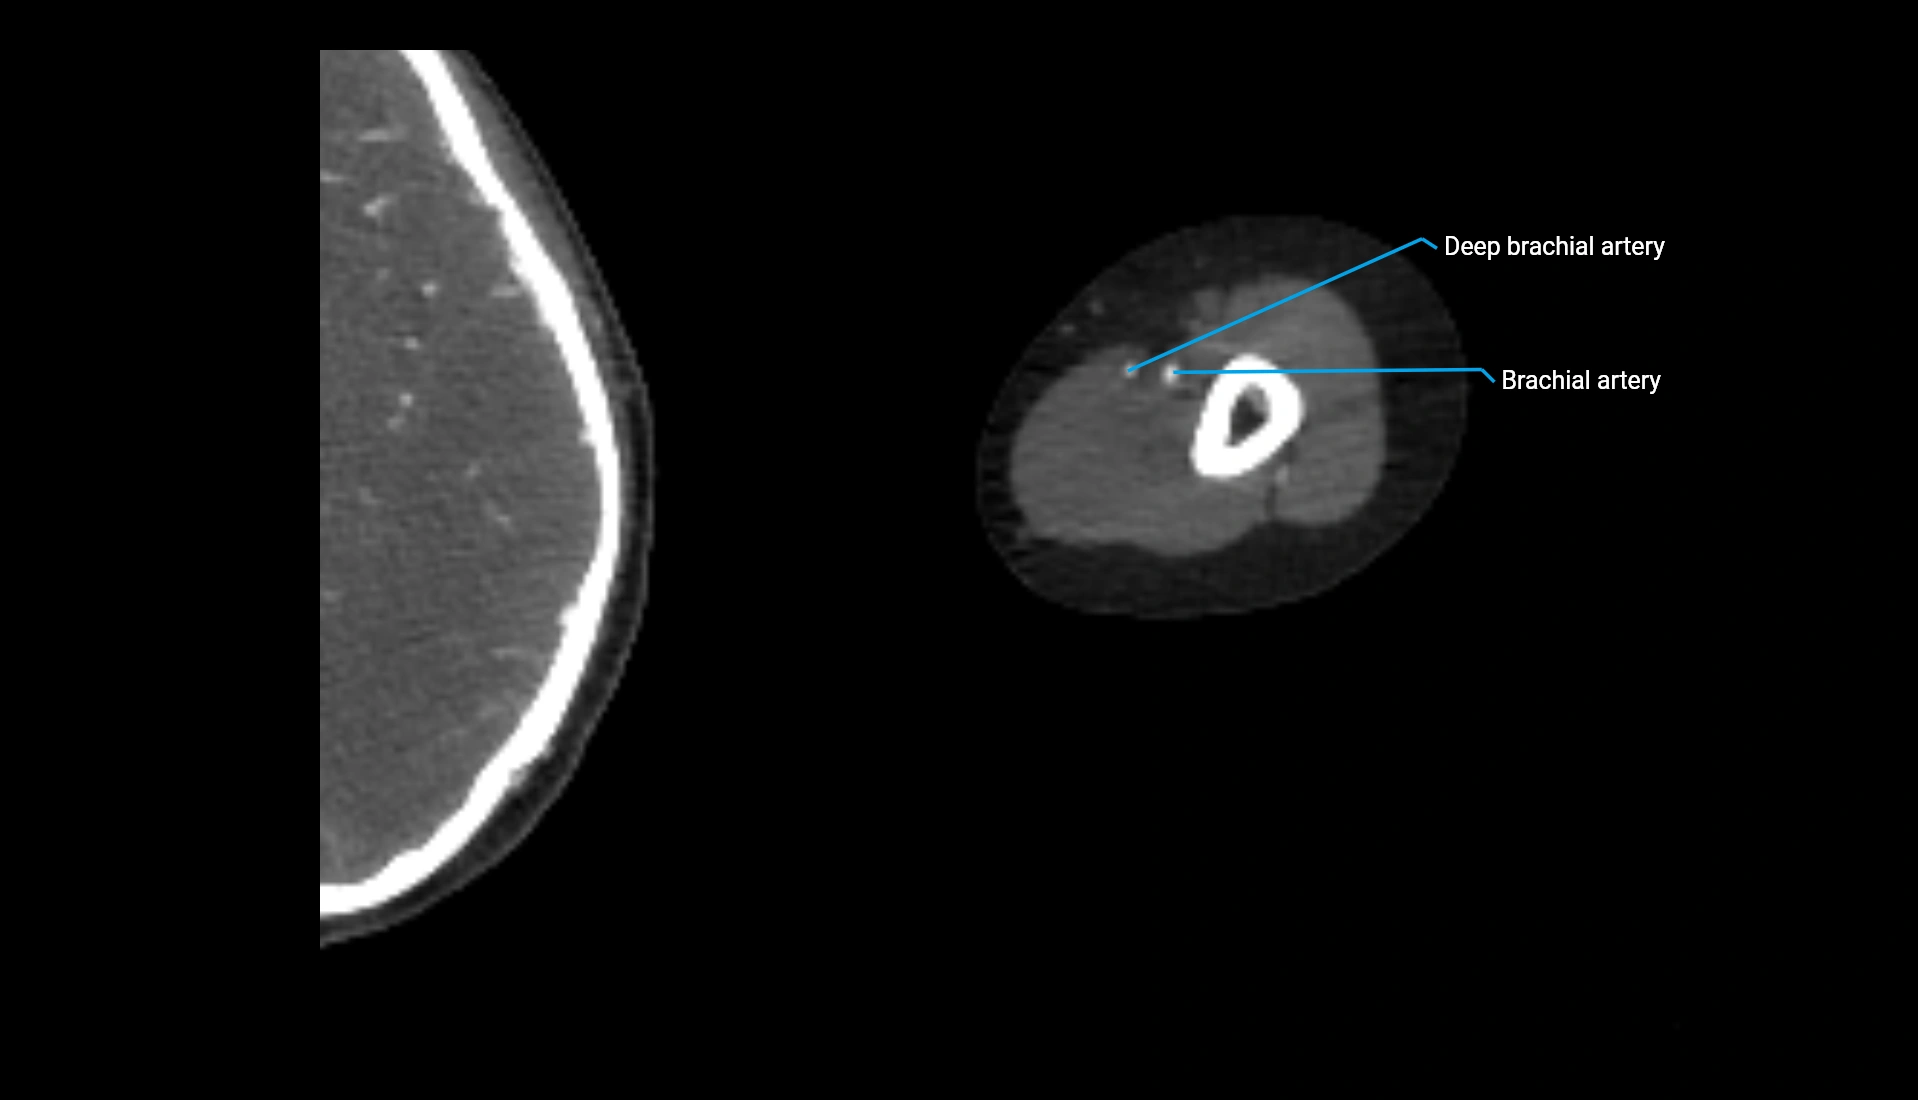

CT Appearance

Non-Contrast CT:

• Cortex: High-density, sharply defined

• Subchondral bone: Dense cancellous matrix

• Articular surface: Smooth concave contour articulating with the capitellum

• Excellent for evaluating bone integrity, alignment, and subtle fractures

Post-Contrast CT:

• Bone: No enhancement

• Joint capsule and synovium: Mild enhancement outlining the joint

• Improves contrast between soft tissues and bony margins

• Useful in detecting subtle joint abnormalities or postoperative changes